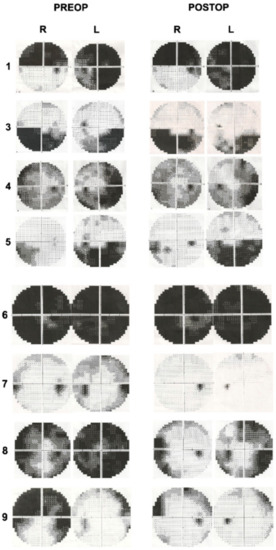

3. Results

Figure 3. Preoperative and postoperative visual field examinations of patients.